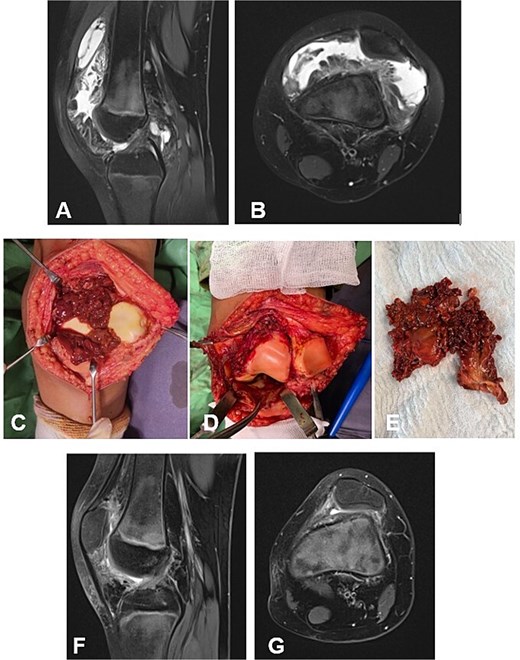

A 9-year-old female presented with a one-year history of knee pain, swelling, and progressive limitation of flexion, unresponsive to nonsteroidal anti-inflammatory drugs and physical therapy. MRI demonstrated a large anterior synovial mass without evidence of bone erosion (Fig. 3A and B). The D-TGCT involved the suprapatellar recess as well as the superior and inferior infrapatellar recesses (Fig. 3C). The pathologically altered synovium was excised en bloc through an open synovectomy (Fig. 3D and E). The hyaline cartilage changes were classified as Outerbridge grade I. At 18 months postoperatively, the patient was asymptomatic, exhibiting full range of motion in the knee. Follow-up MRI revealed no evidence of recurrence of the resected neoplasm (Fig. 3F and G).

Case 2. (A and B) Preoperative Sag and Ax MRI weighted TSE PD FS. (C and E) Macroscopic appearance of the pathological synovium before and after its excision. (D) The knee joint following synovectomy. Chondral lesions correspond to Outerbridge grade I. (F and G) Postoperative 16 m. Sag and Ax MRI TSE PD FS—no evidence of recurrence of the resected neoplasm. Persistent bone marrow edema, though without clinical symptoms. PD FS, proton density weighting with fat suppression; TSE, turbo spin echo.

A 6-year-old girl with a 3-year history of knee pain and swelling, previously treated for Synovitis transitoria. The chronic course of the condition corresponded to progressive limitation of flexion and the development of a flexion contracture (Table 1). The diagnosis was established by MRI (Fig. 4A and B). The D-TGCT involved the central, superior, and inferior infrapatellar synovial recesses (Fig. 4C). Through open synovectomy, the visibly altered synovium was excised en bloc (Fig. 3D and E). The hyaline cartilage changes were classified as grade I according to Outerbridge. One year after surgery, the child remained asymptomatic with a full range of motion in the knee. MRI showed no evidence of recurrence of the excised neoplasm (Fig. 3F and G).

Case 3. (A and B) Preoperative sag and ax MRI TSE PD FS. (C and E) Macroscopic appearance of the pathological synovium before and after its excision. (D) The knee joint following synovectomy. Chondral lesions correspond to Outerbridge grade I. (F and G) Postoperative 12 m. Sag and Ax MRI TSE PD FS—no evidence of recurrence of the resected neoplasm. PD FS, proton density weighting with fat suppression; TSE, turbo spin echo.